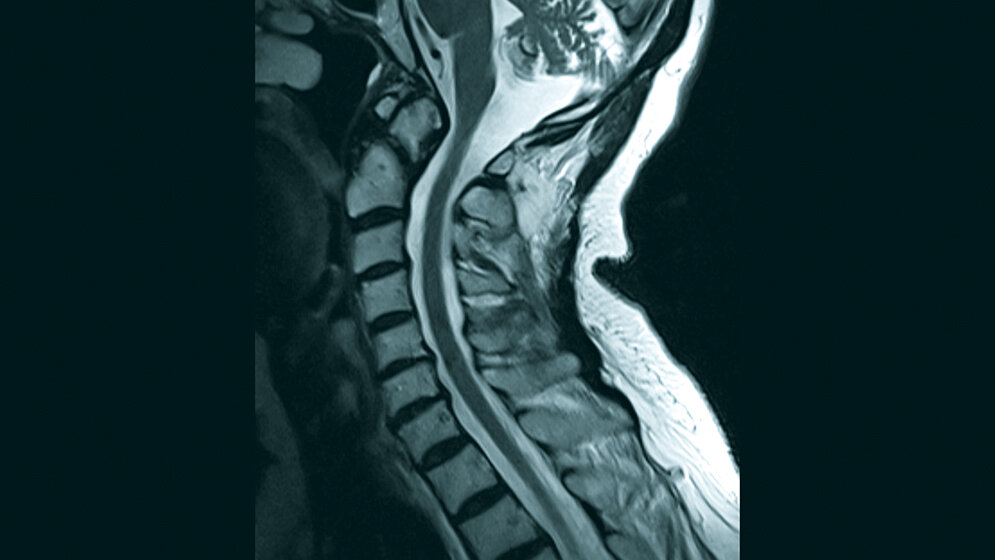

Anomalien des kraniozervikalen Übergangs sind selten. Die Existenz ist bis zum Auftreten klinischer Symptome unbekannt. Mit der kraniozervikalen Anomalie können zahlreiche Syndrome vergesellschaftet sein. Die kongenitalen und erworbenen knöchernen Veränderungen können den kraniozervikalen Bereich alterieren, zur Nerven- und Gefäßkompression führen oder aber auch den Liquorfluss stören. Die Anomalie kann Frakturen des Dens Typ I und II vortäuschen.

Anomalies of the craniovertebral junction are rare. The prevalence is unknown since they may remain clinically silent. A number of syndroms are associated with pathology of the craniocervival junction. Congenital and developmental osseous abnormalities can affect the craniocervical junction complex and can result in neural compression and vascular compromise and can manifest itself with abnormal cerebrospinal fluid dynamics. This anomaly can mimic type I and II odontoid fractures.